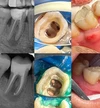

تسوس الأسنان

أمراض الأسنان واللثة